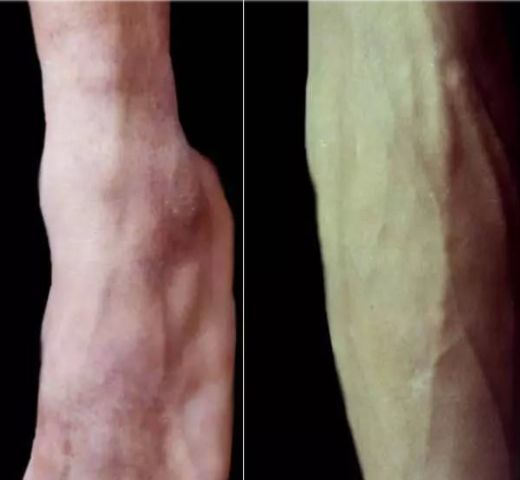

111.下肢孢子丝菌病-淋巴管型

112.下肢孢子丝菌病-淋巴管型(放大照片)